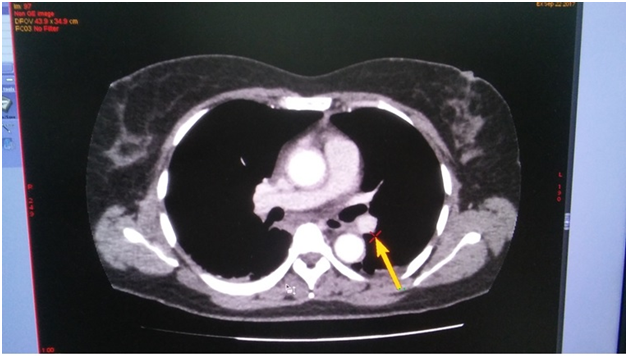

On the next day, at the day time, she felt progressive dyspnea. She was transferred to the intensive care department, where the suggestion of acute lung artery thromboembolic was taken, taken into account the character of dyspnea and extremely low level of blood saturation 60%, with weak response to oxygen therapy. The suggestion was approved by the chest tomography, where the thrombosis of both central lung arteries was revealed (Figure 1-4). After the short discussion among the colleagues, the procedure of thrombolysis was performed. We considered the extremely bad condition of the patient, weak response to oxygen therapy, young age and a kind of the operation. There were no pass to any cavity, no anastomosis, the inserted drainage system, to let blood flow out. Additionally, we had blood cell-save machine “Haemonetics Cell Saver 5+” (USA) to reinfuse blood and decrease blood loss.

Figure 1 (CT of thromboembolism in the left LA).